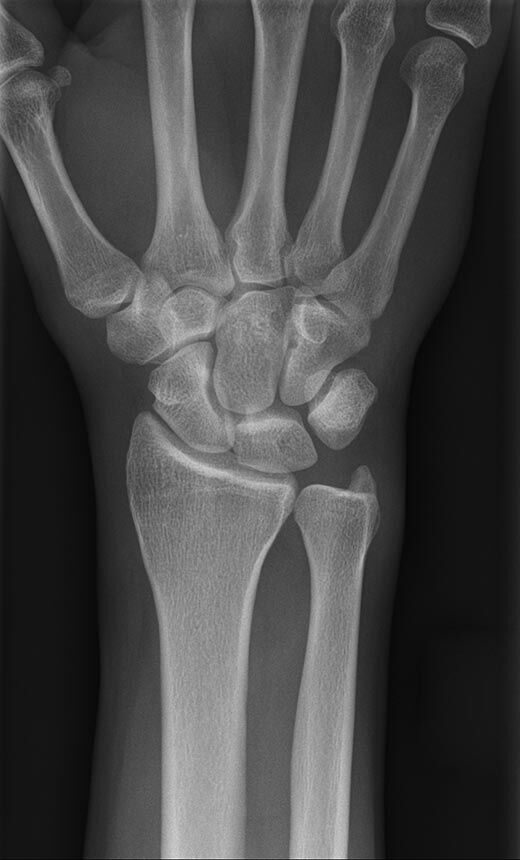

Konventionelles Röntgen

Der Begriff Röntgen, oder auch Röntgendiagnostik bezeichnet ein Verfahren in der Radiologie, bei dem von einer Röntgenröhre elektromagnetische Wellen (Röntgenstrahlen) durch die zu untersuchende Körperregion des Patienten gesendet werden. Je nach Dichte der Gewebeart des Körpers (z.B. Knochen oder Lunge) werden die Röntgenstrahlen im Körper unterschiedlich stark abgeschwächt. Ein digitaler Detektor empfängt dann die Röntgenstrahlen, die in abgeschwächter Form den Körper wieder verlassen haben. Daraus wird das Röntgenbild erzeugt.

Die zu untersuchenden Anteile des Körpers werden meistens

in 2 unterschiedlichen Projektionsebenen dargestellt.

In einigen Körperregionen sind spezielle Zielaufnahmen notwendig.

Die Röntgenuntersuchung ist weiterhin eine unverzichtbare Basisdiagnostik. Viele Fragen können in der medizinischen Diagnostik mit einer konventionellen Röntgenaufnahme geklärt werden.